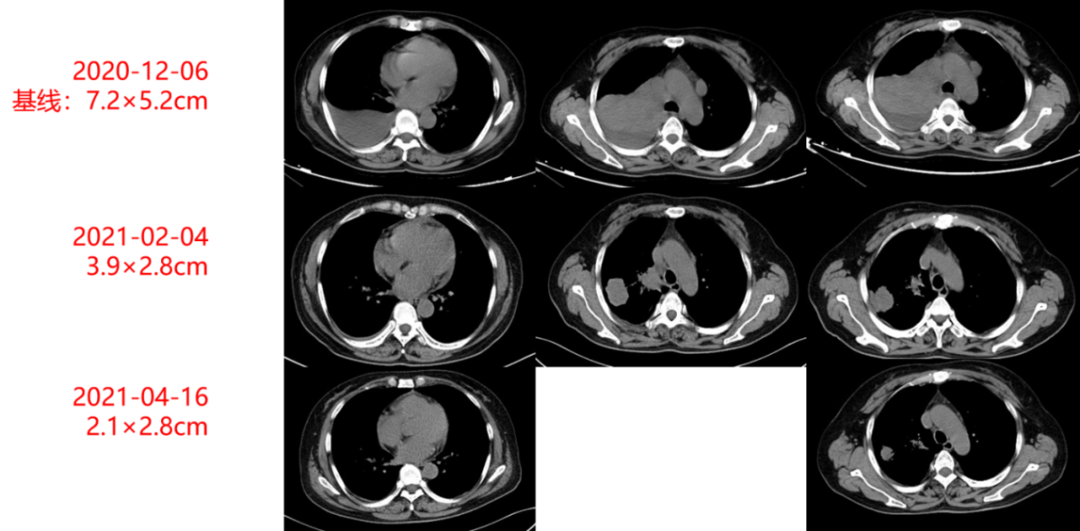

影像学及疗效评价:患者治疗期间定期复查胸部CT,见右肺原发灶逐渐缩小(如图1-2及1-3所示),末次复查时病灶大小为2.1×2.8cm,疗效评价持续PR。

图1-2:治疗期间胸部CT动态变化(肺窗)

图1-3:治疗期间胸部CT动态变化(纵隔窗)

本例患者主因“胸痛1月”就诊,完善相关检查诊断为肺腺癌(T4N2M1,Ⅳ期)伴肺内外多发转移。考虑到患者分期较晚,根治性手术无法切除,先行予患者进行单纯化疗,同时完善基因检测及免疫治疗预测指标,提示患者有TP53基因变异、PD-L1蛋白表达阳性肿瘤细胞占比+(100%),故后续治疗方案调整为化疗+免疫+抗血管生成方案,即培美曲塞+卡铂+替雷利珠单抗+贝伐珠单抗。患者治疗期间规律复查胸部CT,原发病灶体积逐渐缩小(从7.2×5.2cm逐渐缩小至2.1×2.8cm),CEA逐渐降至正常水平(如图1-4所示),疗效持续PR。治疗期间,患者安全性及耐受性良好,未出现明显治疗相关不良反应。